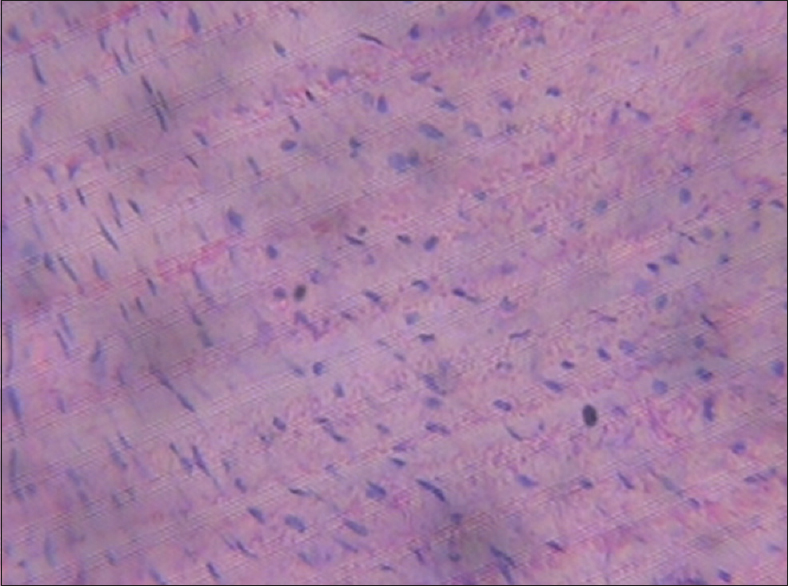

Figure 8: Heart (1250 mg/kg of monosodium glutamate)